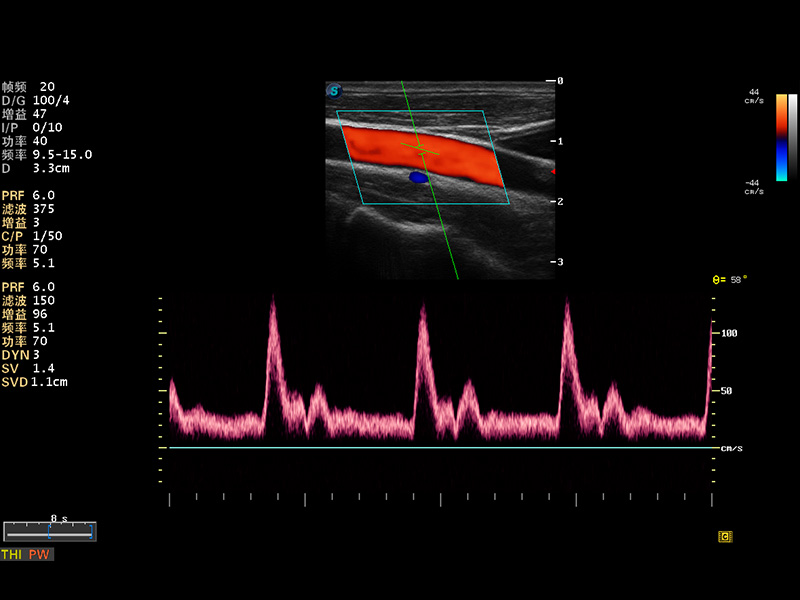

S8 EXP便携式彩色多普勒超声诊断仪是哈哈体育官网研发的高端全身应用型便携彩超。高通道的VIS平台融合可视化(Visual)、智能化(Intelligent)和人性化(Smart)的特点,配以哈哈体育官网自主研发生产的探头大家族,使您能够快速、准确的获得病人信息,提高工作效率的同时减轻疲劳。

多波束形成器

μ-Scan微米成像